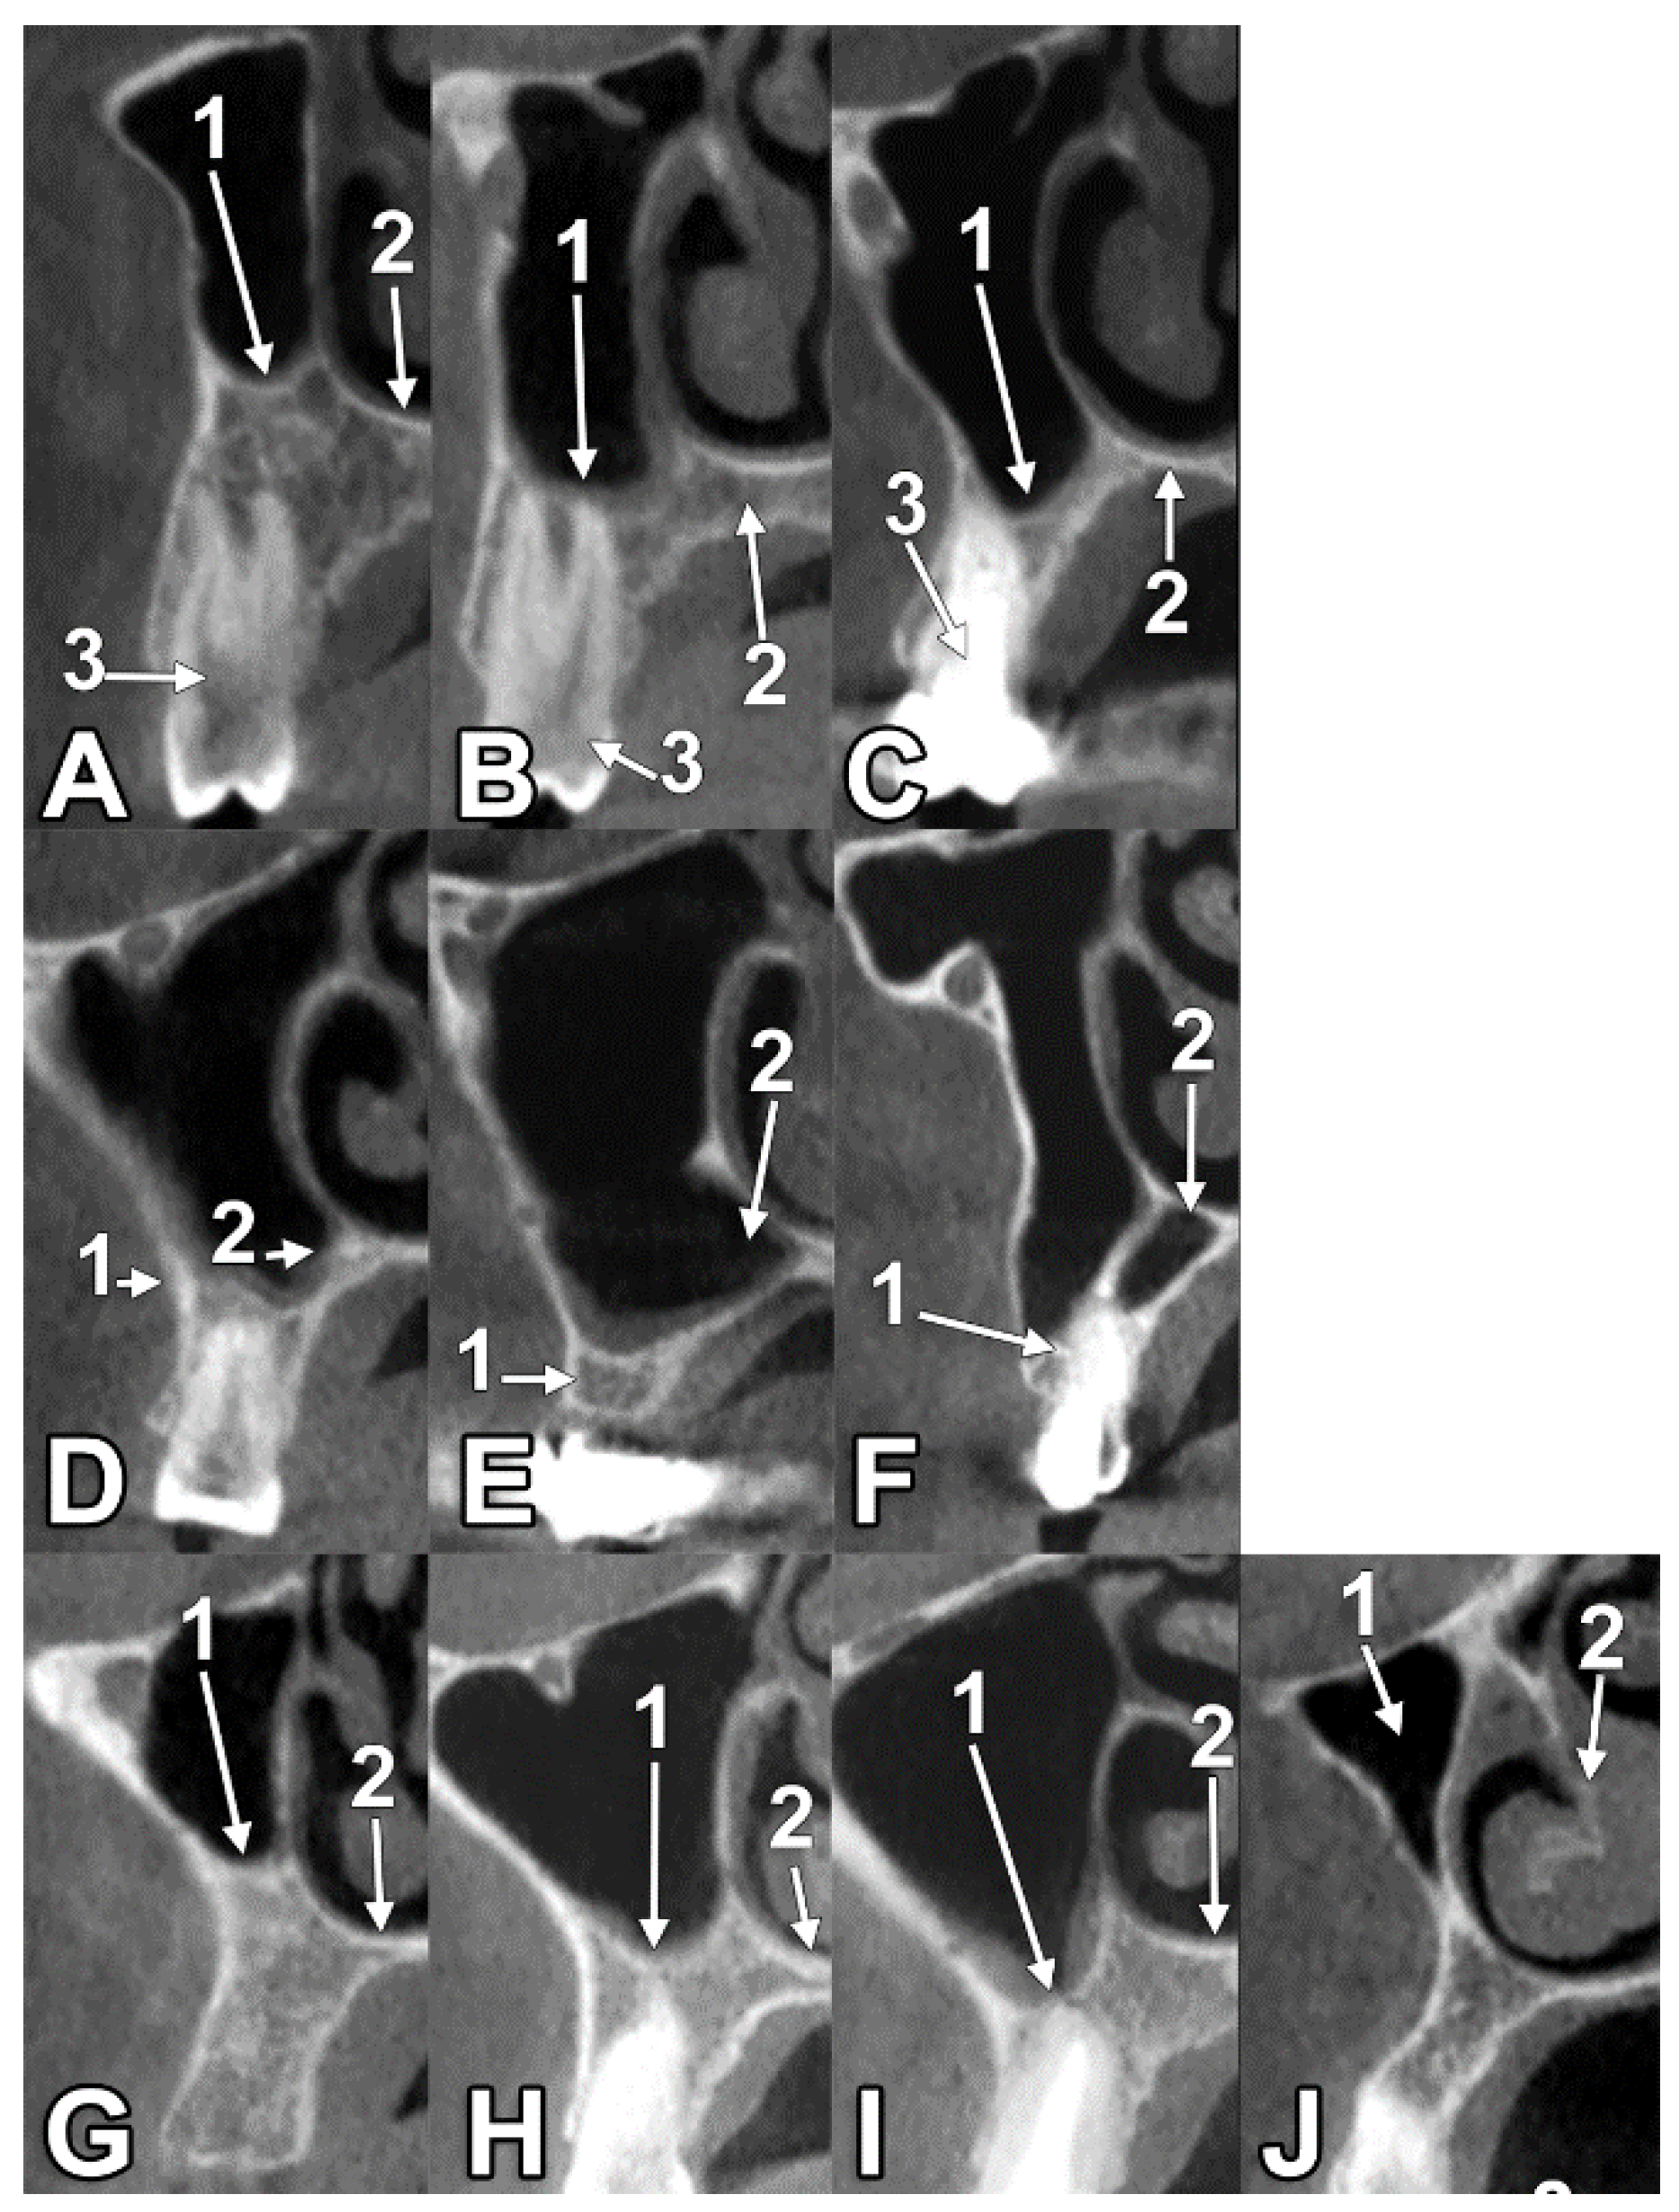

3.1. Types of the Antral Floor

3.2. Alveolar Base Morphometry in Types 2 and 3